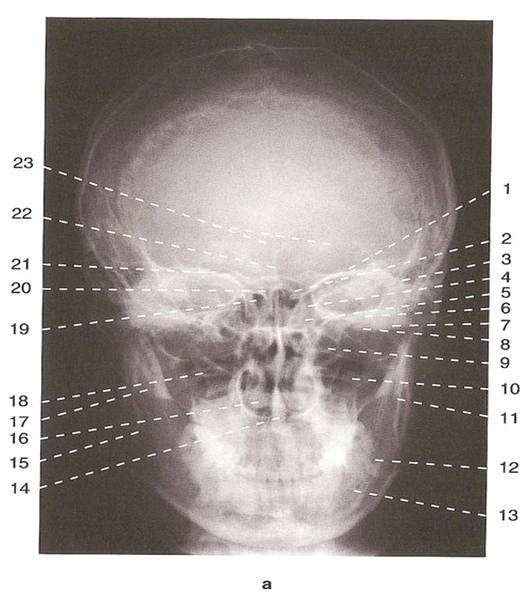

Анатомические изображения срединной сагиттальной линии черепа